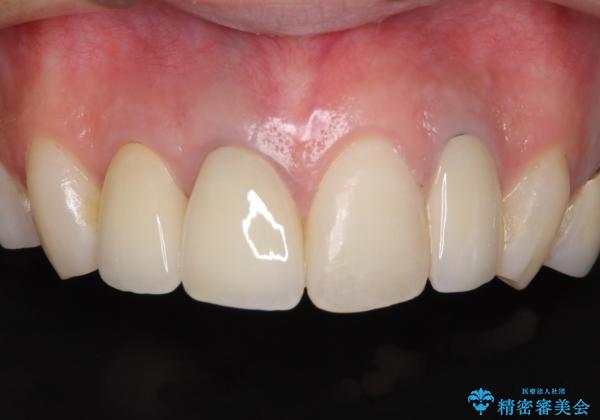

色調を統一するために、未治療の1歯もクラウンを装着するかどうか悩んでいらっしゃいましたが、結果としては治療せずに4前歯の色調を合わせることができました。

歯肉の黒ずみも多少改善させることができ、患者様には大変満足していただきました。